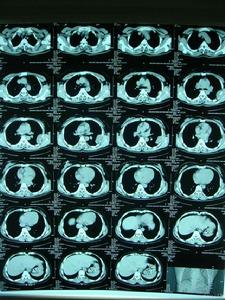

在制定手術方案時,須精確確定腫瘤在骨髓腔內或松質骨內的侵襲範圍,可藉助於骨掃描、CT和MRI。

如肺轉移瘤局限,應行肺轉移瘤切除。

中心性軟骨肉瘤傾向於向阻力較小的地方擴張,如骨幹的髓腔。在幾乎一半的病例中,放射影像顯示腫瘤侵犯整個長骨的1/3、1/2或更多,但在腫瘤早期,影像上可能無顯示。這個特點很重要,否則手術方案可能不恰當,切除緣可能不夠,於骨幹切除或截肢術後殘肢處腫瘤可復發,為避免發生,須在術前通過骨掃描、CT和MRI來確定腫瘤在髓腔內的範圍。